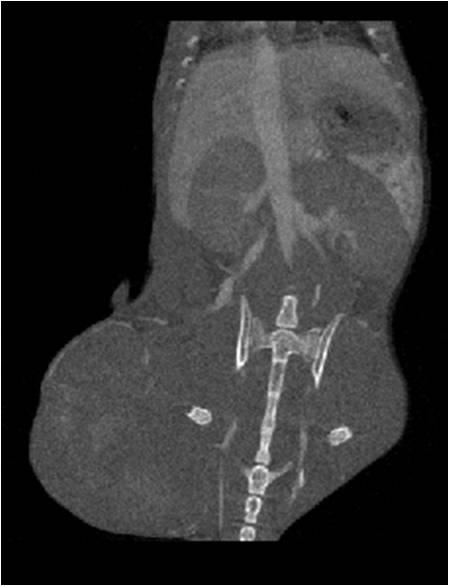

肺轉移

小鼠模式,22.5μm像素

正常

8天 14天

無造影劑注入 造影劑注入